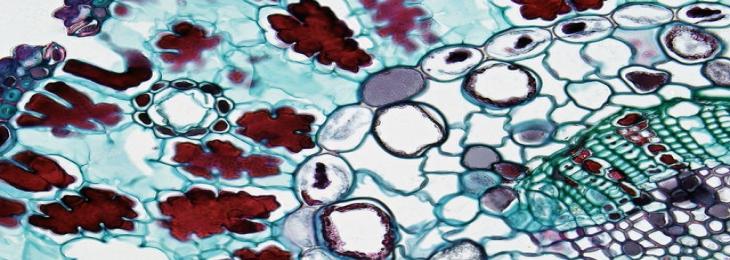

A new study found that specific type of gut bacteria hoard consumed drugs restricting their efficiency. There are numerous bacteri...

A new study found that specific type of gut bacteria hoard consumed drugs restricting their efficiency. There are numerous bacteri...